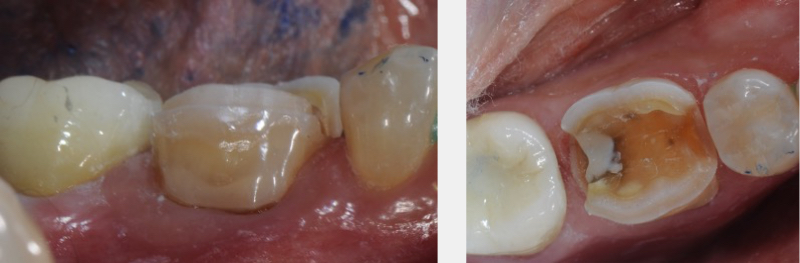

In many circumstances, posterior partial coverage restorations replace pre-existing large, old fillings. Many of these old restorations include a significant portion of the occlusal surface and extend into the interproximal areas. The resultant partial coverage tooth preparation then contains interproximal “boxes” following removal of the old filling material.

These “boxes” aid in retention of the provisional restoration by promoting resistance to dislodgement. A conventional provisional cement may be utilized (Kerr’s Temp-Bond or Caulk Fynal are examples of these more conventional provisional cements).

Alternatively, there can be situations where no preexisting restorations exist, and there is a need to “contain the cusps” to manage fractures and cracks within the teeth. These minimal partial coverage restorations become very challenging to predictably provisionalize.